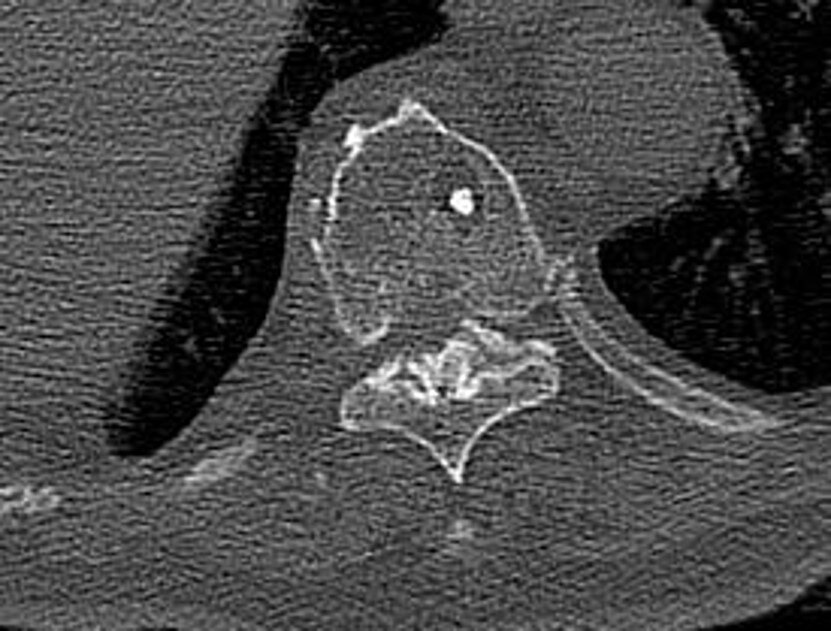

●腰の激痛 椎間板ヘルニア・ギックリ腰・すべり症・分離症・圧迫骨折 腰と脊椎の名医が教える 最高の治し方大全 聞きたくても聞けなかった150問に専門医が本音で回答! ISBN : 9784866512747 著者 : 菊地臣一…